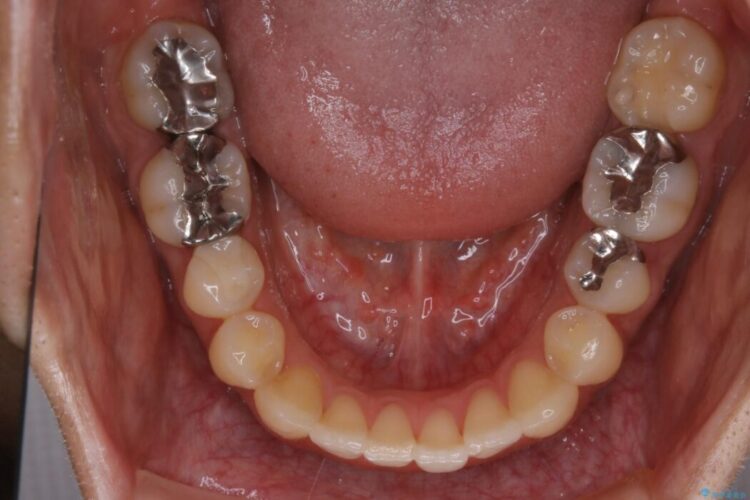

目立たない矯正装置をご希望でしたのでマウスピース装置(インビザライン)をご提案しました。

装置の範囲内で可能な限り前歯の位置を動かし整えるため、マイクロインプラントを用いて遠心移動をする歯列矯正を計画しました。

本症例では上顎前突(出っ歯)や歯列のがたつきを改善するスペースを確保するために、歯を遠心移動をサポートすることができるマイクロインプラントを用いたゴムかけを行っていただきました。

それにより従来の矯正治療と比べましても効率的に歯の移動を行えるため、非抜歯の場合でも歯列を整えることが可能となります。